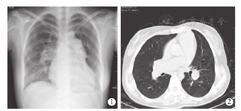

受者为女性,26岁,体重52 kg,身高167 cm,5岁时发现心脏杂音,当时诊断"先天性心脏病,房间隔缺损" ,无明显缺氧体征未予特殊处理,10岁后出现反复气促,14岁始出现活动耐力下降、紫绀等症状,外院诊断"先天性心脏病(艾森曼格综合征,房间隔缺损,重度肺动脉高压)" 。受者于2015年5月25日入院,经胸部X线片(图1)、胸部CT检查(图2)、心脏彩色超声检查等影像学相关检查以及其他实验室相关检查后,明确诊断:(1)先天性心脏病:房间隔缺损(下腔型),肺动脉高压(重度), 三尖瓣关闭不全(重度),窦性心律,完全型右束支传导阻滞,心功能Ⅳ级;(2)艾森曼格综合征。拟行房间隔缺损修补术同期双肺移植术。术前肺功能检测显示:极重度限制性通气功能障碍,用力肺活量(FVC)占预计值26.5%,一秒用力呼气容积(FEV1)占预计值22.5%,FEV1与FVC比值(FEV1/FVC)为84.9%。术前漂浮导管测得数据:肺动脉阻力12 Wood,平均肺动脉压92 mmHg,肺毛细血管楔压100 mmHG。